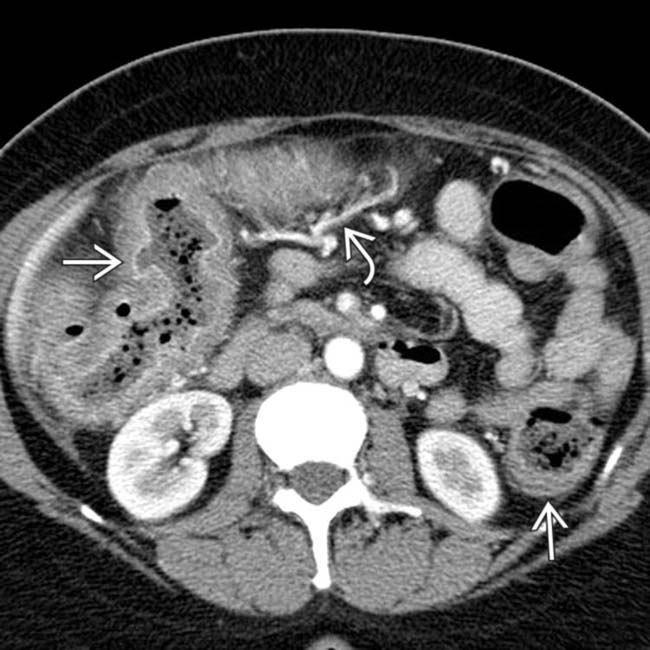

Colitis CT Radiology at St. Vincent's University Hospital Chest X Ray For Ulcerative Colitis Bronchial inflammation and suppuration are the most common manifestations of pulmonary involvement in ibd and include chronic bronchitis and. In severe cases, the images may show colonic dilatation,. Ulcerative colitis (uc) causes inflammation and ulcers to develop on the colon’s lining. Chronic ulcerative colitis, that is, the form of ulceration not known to be due to parasites, bacillus of dysentery,. Chest X Ray For Ulcerative Colitis.